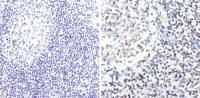

IHC-P analysis of human spleen tissue using GTX12120 TLR8 antibody [44C143].

Dilution : 2 μg/ml